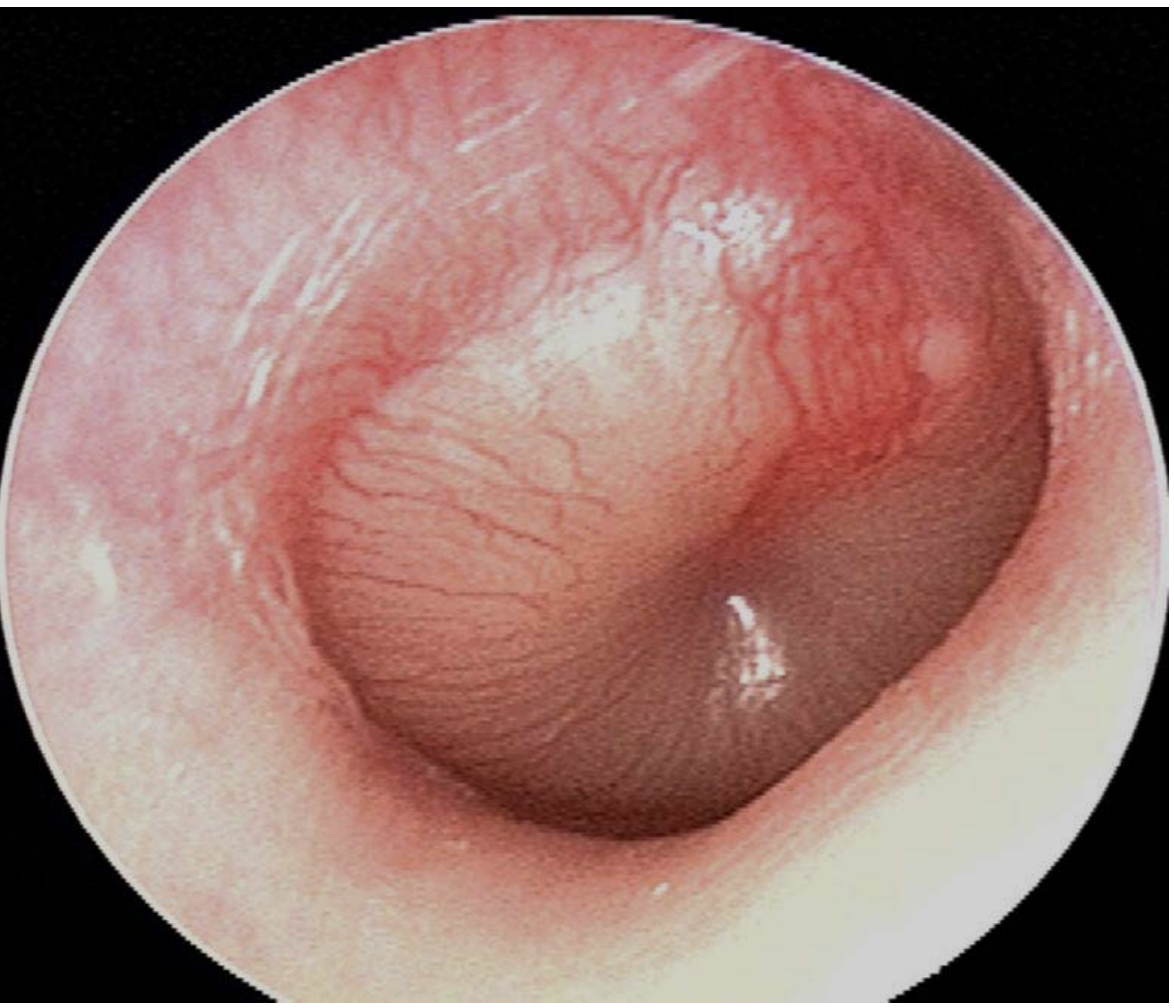

What is the diagnosis and three supportive findings?

Acute suppurative otitis media

1. Bulging TM

2. Erythematous TM

3. pus behind TM